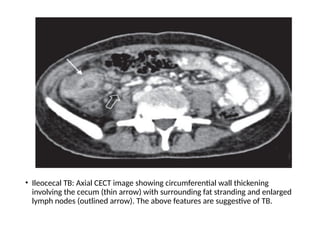

• Ileocecal TB: Axial CECT image showing circumferential wall thickening

involving the cecum (thin arrow) with surrounding fat stranding and enlarged

lymph nodes (outlined arrow). The above features are suggestive of TB.

• Ileocecal TB:Axial CECT image showing circumferential wall thickening involving the cecum (thin arrow) with surrounding fat stranding and enlarged lymph nodes (outlined arrow). The above features are suggestive of TB.